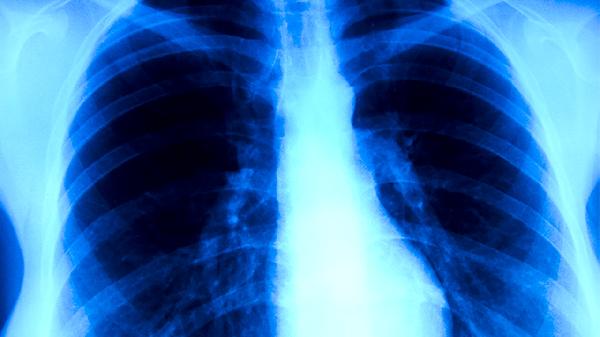

中醫(yī)將肺結(jié)核歸為肺癆范疇,病機(jī)以肺陰虧虛為主。麥冬、沙參、百合等滋陰潤肺藥材可緩解干咳;黃芪、黨參等補(bǔ)氣藥能改善盜汗乏力。臨床常用百合固金湯、月華丸等方劑,需連續(xù)服用2-3個(gè)月。

常見輔助方劑含生地12克、玄參10克滋陰,川貝6克化痰,三七3克止血??┭獓?yán)重可加白茅根15克,骨蒸潮熱配地骨皮10克。需根據(jù)舌脈變化每周調(diào)整藥方,配合西藥需間隔2小時(shí)服用。

肺結(jié)核康復(fù)期可飲用沙參玉竹茶養(yǎng)陰,羅漢果茶潤喉。適度快走增強(qiáng)心肺功能,避免劇烈運(yùn)動(dòng)耗氣傷陰。艾灸肺俞穴、膏肓穴提升免疫力,但發(fā)熱期禁用。需完成全程化療,痰菌轉(zhuǎn)陰后仍需鞏固治療,擅自停藥易導(dǎo)致耐藥性結(jié)核。定期胸片復(fù)查,密切觀察藥物不良反應(yīng),中西醫(yī)結(jié)合治療可降低復(fù)發(fā)風(fēng)險(xiǎn)。